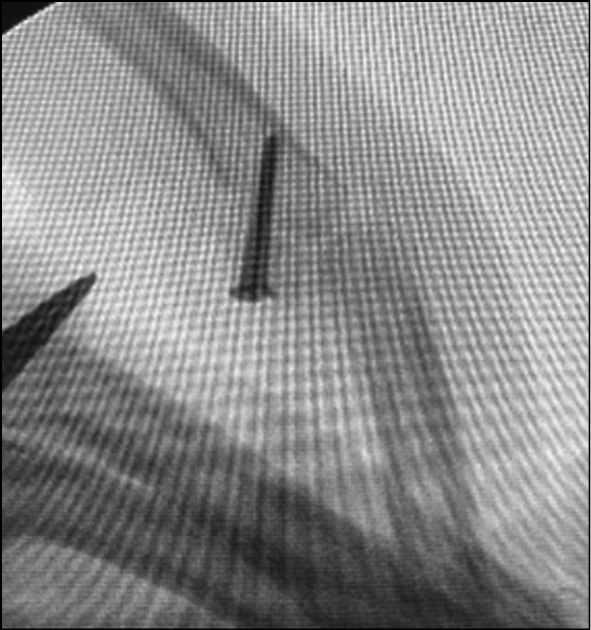

Fig. 6. X-ray control after fixation of the graft with screws.

Fig. 7. Intraoperative picture after fixation of the graft with screws.

Fig. 26. X-ray control after surgery. Suzuki pins and rubber traction system.

Fig. 27. Appearance after surgery. Suzuki pins and rubber traction system.